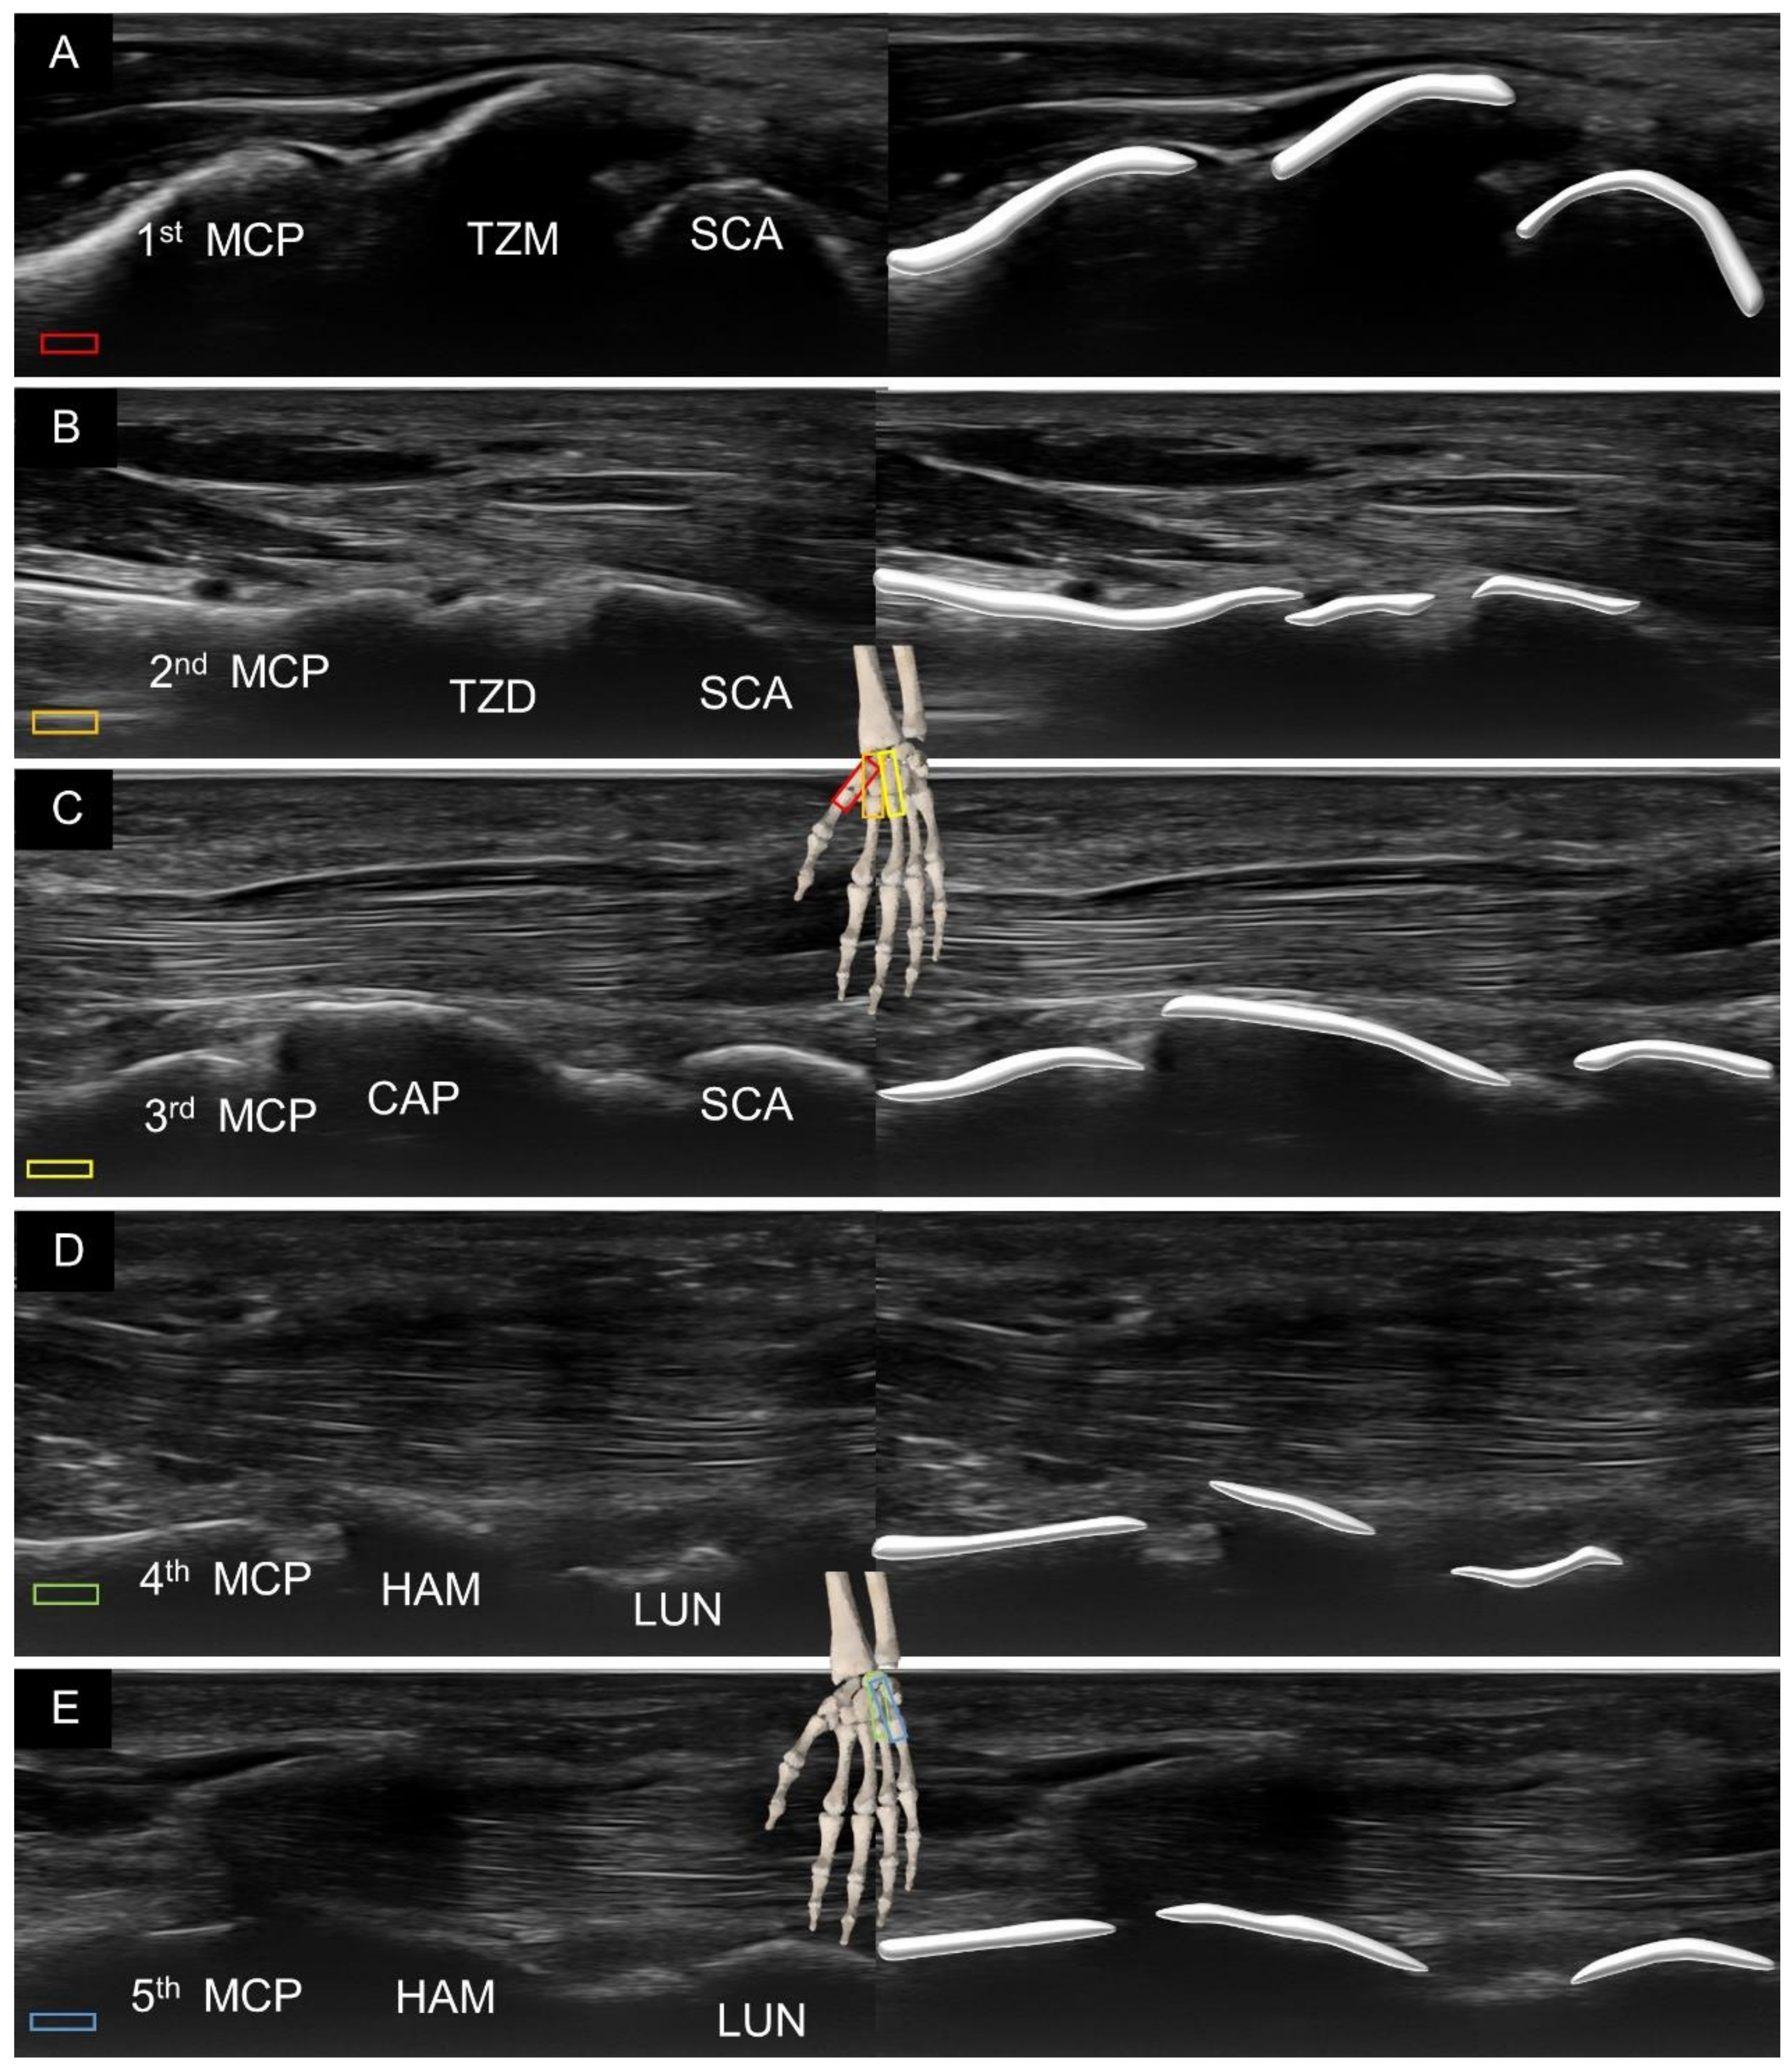

3. Sonoanatomy of Volar Extrinsic Carpal Ligaments

3.1. Attachment to the Capitate

3.2. Attachment to the Lunate

3.3. Attachment to the Triquetrum